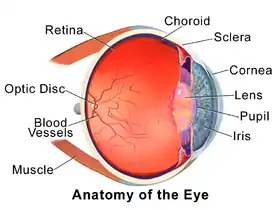

| Choroid | |

Cross-section of human eye, with choroid labeled at top. | |

The choroid, also known as the choroidea or choroid coat, is a part of the uvea, the vascular layer of the eye. It contains connective tissues, and lies between the retina and the sclera. The human choroid is thickest at the far extreme rear of the eye (at 0.2 mm), while in the outlying areas it narrows to 0.1 mm.[1] The choroid provides oxygen and nourishment to the outer layers of the retina. Along with the ciliary body and iris, the choroid forms the uveal tract.

Schematic cross section of the human eye; choroid is shown in purple.

Schematic cross section of the human eye; choroid is shown in purple. Laser Doppler imaging of retinal and choroidal blood flow